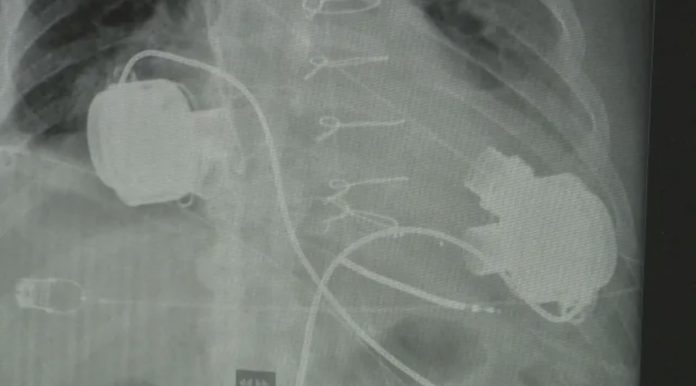

Веднага е свикан консилиум от кардиохирурзи, реаниматори и интервенционални кардиолози, който на базата на предоставената информация и обективното състояние на пациента е взел решение за поставяне на устройства (два броя) за изкуствено подпомагане на кръвообръщението – Heart mate III.

Допълнително предизвикателство представлява факта, че само с едно изкуствено сърце не може да се осъществи достатъчно циркулация на кръв в тялото и след запитване и разрешение от НЗОК се е преминало към имплантация на две устройства, съответно подпомагащи лявата и дясната камера на сърцето.